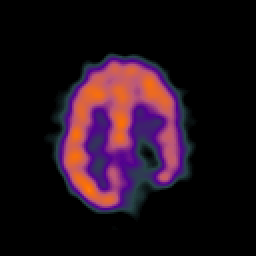

SPECT TC Study #7 -- Slice #39

[Home][Help][Clinical][Tour 1][Tour 2][Tour 3] Slice 39